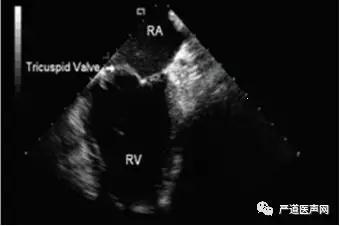

第一步,Mid-RA位置视野:经股静脉穿刺,将3D-ICE导管送入右房中位(mid-RA),以扇面指向12点钟方向为基准,通常顺时针旋转15°,能清楚看见三尖瓣环,此视野又称为home view,如图2。

图2 Mid-RA位置视野(home view)